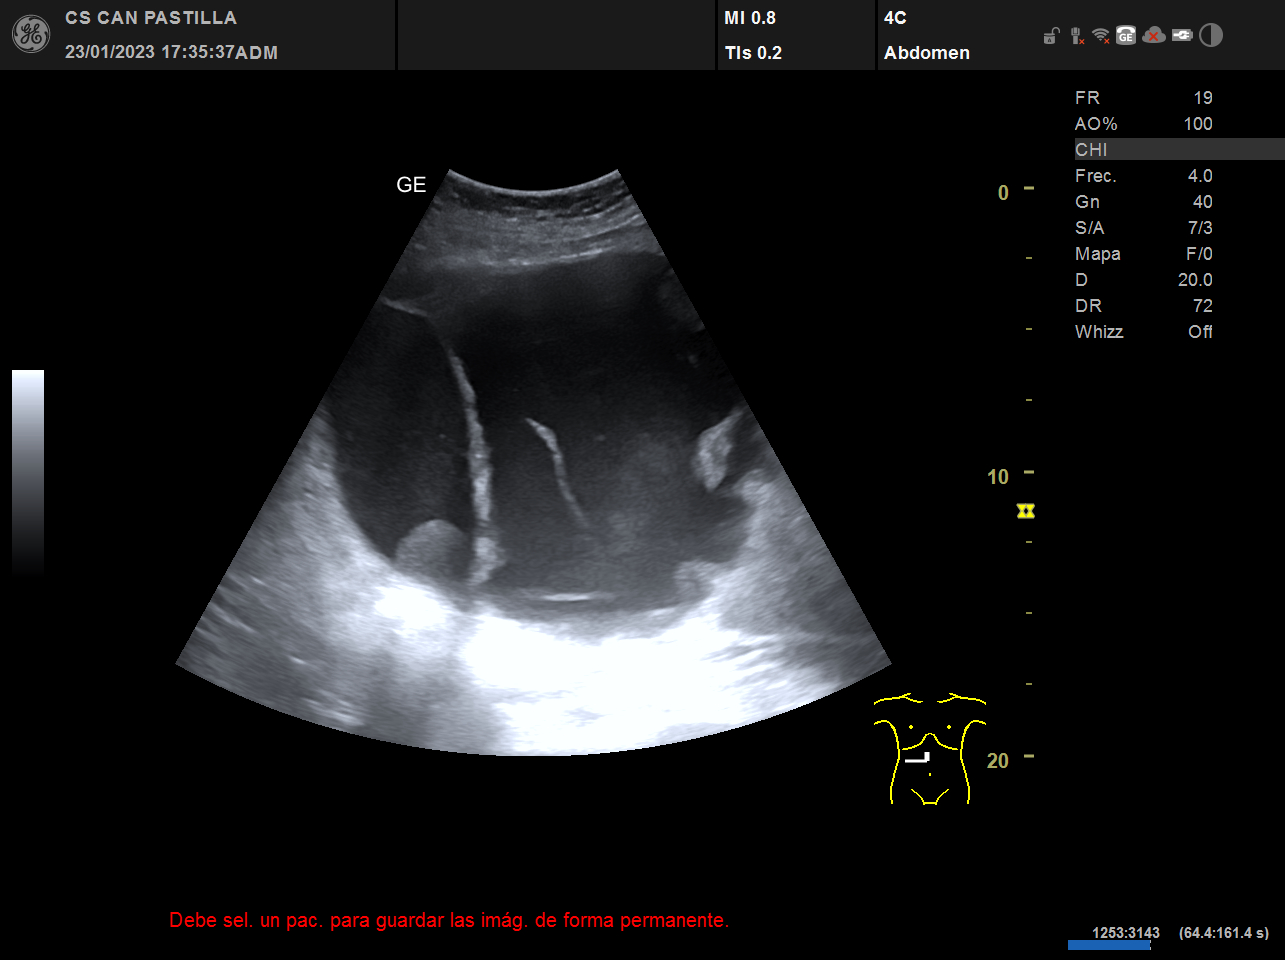

ECO abdominal: destacan imágenes anecóicas con refuerzo acústico posterior y septos en su interior, sugestivas de quistes complejos de gran tamaño (el mayor de ellos de 15 cm de diametro) o un solo quiste tabicado de gran tamaño. Dificultad para observar el parénquima hepático de forma completa, dados la ocupación de las imágenes quísticas.